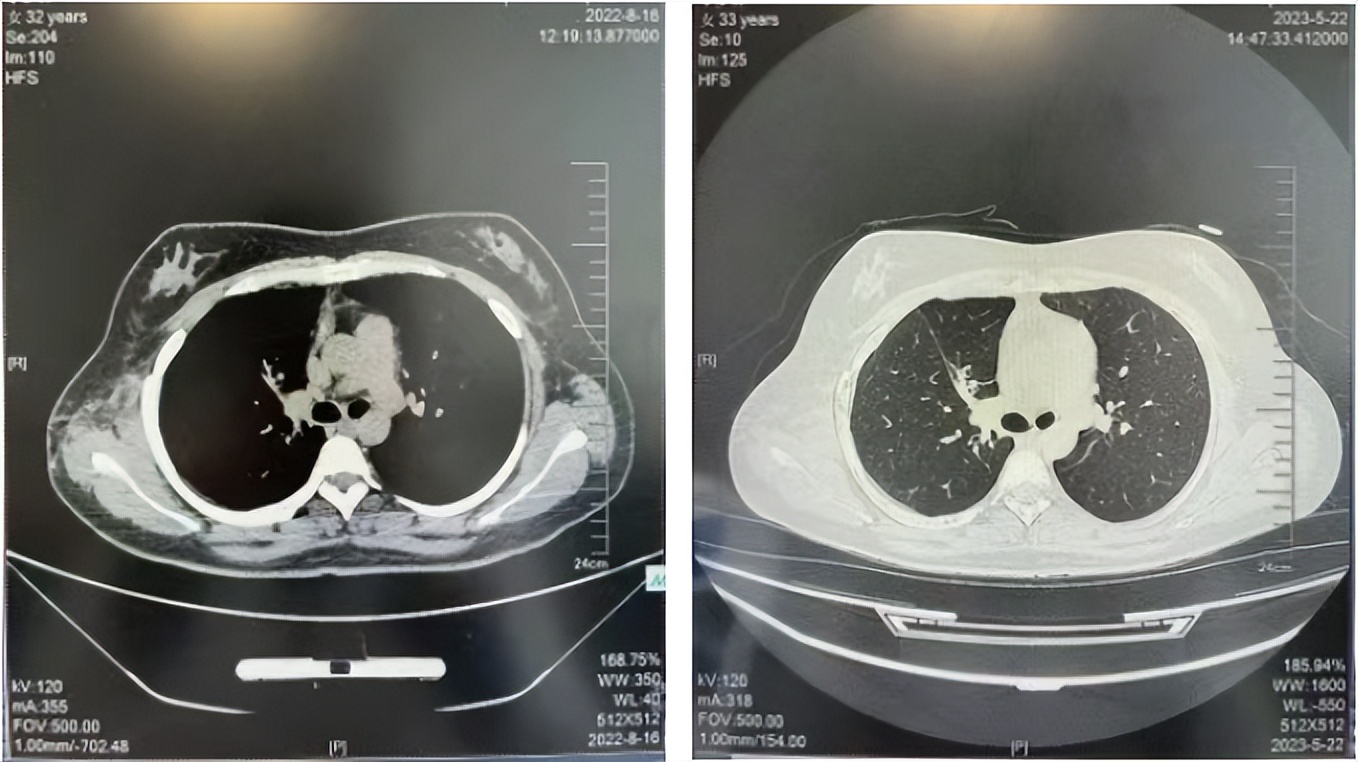

2016年1月复查CT提示支气管截断可见新发小结节,一线治疗采用培美曲塞+DDP方案化疗4周期(培美曲塞3.36,DDP 480mg)。化疗后复查胸部CT:右肺见不规则结节样影,最大层面大小约19mm*8mm,较前比较明显增大,疗效评估PD。2017.3-2017.4予单药多西他赛化疗3周期,疗效评估SD。2018年5月末复查CT提示结节较前增大,评效为PD,2018年6-10月予多西他赛+CBP化疗4周期,疗效评估SD。2022年5月患者出现活动后气短,复查胸部CT示右肺膨胀不良;右侧胸腔积液增多。胸腔积液包埋病理示符合肺腺癌细胞。行NGS基因检测:EML4:exon13-ALK:exon20融合。PD-L1(克隆号22C3)TPS<1%。

2018.07

2022.05

2022.08

2023.05